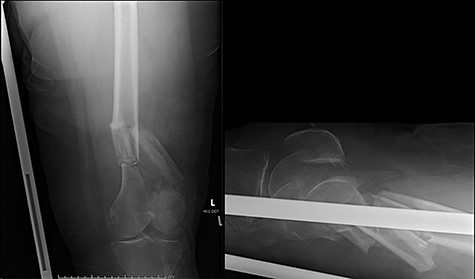

The cases of failure are here examined in more detail. Case 1 (Figs 1 and 2): this active gentleman was paddleboarding off the Llŷn peninsula when he was knocked onto his side by a wave.

Fracture above plate tip following successful union for Case 1.

Clearly, this has occurred following on from successful union. Despite a sound original fixation, the rigid construct has acted as a lever-arm to produce a fracture above the plate tip. In long spiral fracture configurations such as this, antegrade intra-medullary nailing could be considered as the primary treatment modality.